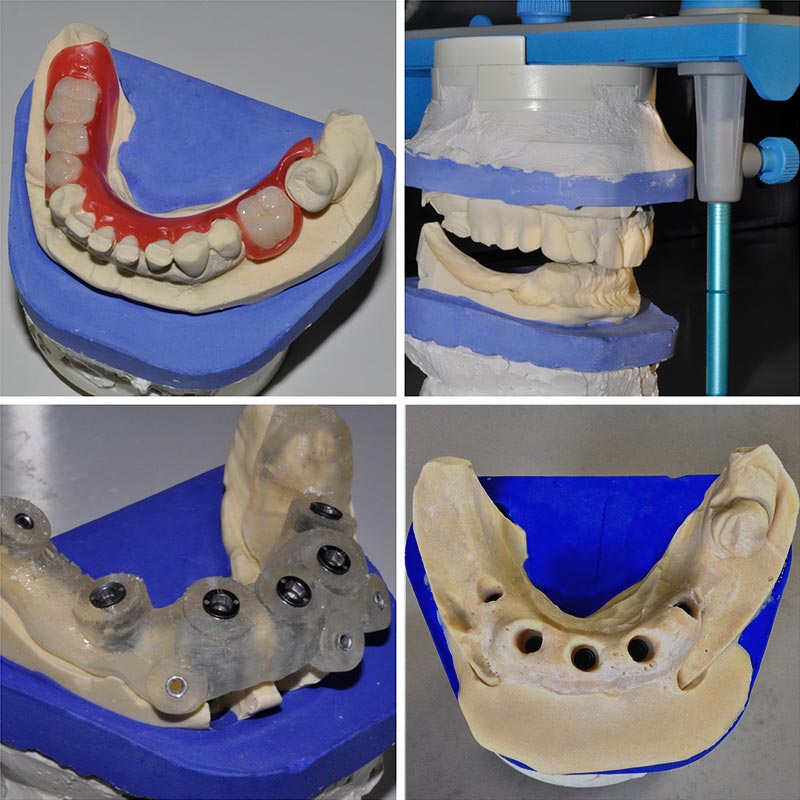

Fig. 01 : création d’un modèle de travail d’après les données de la planification selon un protocole traditionnel en se servant du guide chirurgical comme outil de repositionnement des répliques d’implants.

De nombreuses solutions ont été testées avec plus ou moins de réussite, comme la réalisation de modèle de travail en positionnant les répliques d’implants grâce au guide chirurgical pour réaliser la prothèse en amont de l’intervention (fig. 01) puis l’utilisation de gouttière pour repositionner sur l’arcade la restauration dès la fin de l’intervention (fig. 02) pour éviter une empreinte sur des tissus fragilisés et priver le patient de dents pour une voire deux journées.

Fig. 02 : gouttière de repositionnement pour transférer la prothèse transitoire de l’articulateur à l’arcade du patient.